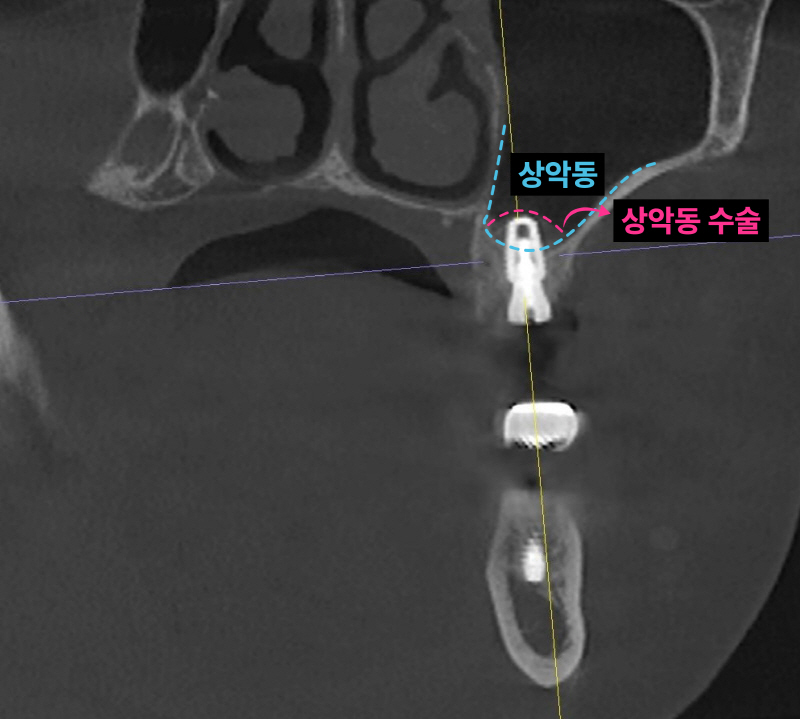

남아있는 잇몸뼈가 5-6mm 정도입니다. 저는 이런한 경우 덴샤버라는 특수한 기구를 이용해서 가능한 빠르면서 안아프고 쉽게 상악동 수술을 시행합니다. 항상 CT를 통해 환자분들께 정확하게 수술된 모습을 보여드립니다.

발치, 상악동 거상, 임플란트 식립 모두 이상적인 모습입니다. 과거 임플란트가 없던 시절에는 브릿지 치료가 일반적이었습니다. 하지만 현재는 치아가 없을 때 양 옆의 치아를 갈아서 씌우는 치료는 임플란트 등장으로 없어지고 있습니다. 또한 오래된 브릿지가 흔들리거나 잇몸에 염증이 생긴다면 임플란트로 교체가 필요할 수 있습니다.